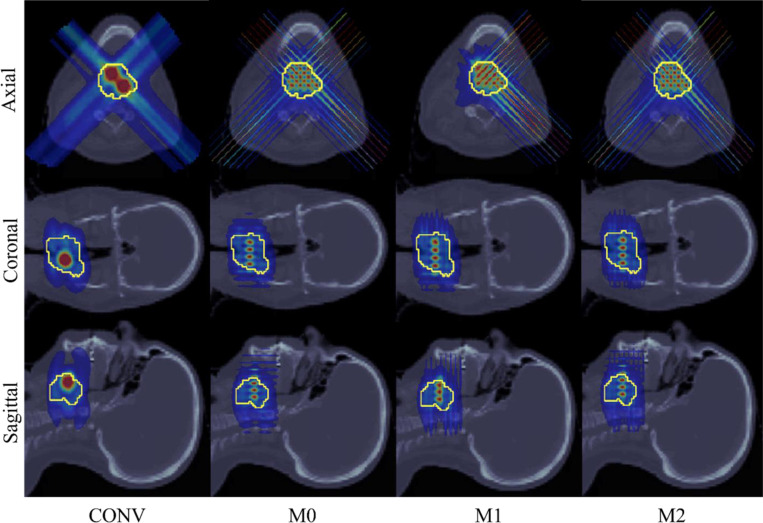

Methods: Three minibeam-pLATTICE methods are introduced. (1) M0: a fixed minibeam aperture orientation (e.g., 0°) for all beam angles; (2) M1: alternated minibeam aperture orientations (e.g., between 0° and 90°), for consecutive beam angles; (3) M2: multiple minibeam aperture orientations (e.g., 0° and 90°) for each beam angle. The purpose of M1 or M2 is to correct anisotropic dose distribution at lattice peaks due to the planar spatial modulation of minibeams. For each minibeam-pLATTICE method, an optimization problem is formulated to optimize dose uniformity in target peaks and valleys, as well as dose-volume-histogram-based objectives. This optimization problem is solved using iterative convex relaxation and alternating direction method of multipliers (ADMM).

Results: Three minibeam-pLATTICE methods are validated to demonstrate the feasibility of minibeam-pLATTICE for two clinical head-and-neck (HN), one abdominal and one brain case. The advantages of this modality over conventional beam (CONV) pLATTICE are evaluated by comparing peak-to-valley dose ratio (PVDR) and dose delivered to organs at risk (OAR). All three minibeam-pLATTICE modalities achieved improved plan quality compared to CONV, with M2 yielding the best results. For instance, in one HN case, the following improvements were observed: PVDR increased to 3.73 (M2), compared to 3.27 (CONV), 3.72 (M0), and 3.49 (M1), while the mean dose to the mandible was reduced to 0.18 Gy (M2), compared to 0.33 Gy (CONV), 0.17 Gy (M0), and 0.14 Gy (M1).